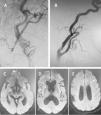

It is an increasingly common practice to indicate a carotid endarterectomy procedure based on the information provided by non-invasive tests like Duplex ultrasound, MR angiography or CT angiography, thereby obviating the performance of a conventional cerebral angiography. We present a case of symptomatic left carotid artery 80% stenosis in which cerebral angiography showed absence of the right A1 segment and bilateral anterior cerebral artery territories that filled only from a left injection. Just 90seconds after carotid artery clamping at the neck, brain oximetry and somatosensory evoked potentials significantly dropped, that recovered after immediate clamp removal. Endarterectomy was dismissed and a carotid stent was successfully placed. This case highlights the importance of knowing the dynamics of cerebral blood circulation distal to the stenosis. If endarterectomy had been attempted, unawareness of the information provided by the cerebral angiography would have likely result in severe bi-hemispheric ischemia.

Cada vez es más frecuente indicar una endarterectomía carotídea en función de la información proporcionada por pruebas no invasivas, como la eco-Doppler, la angio-RM o la angio-TAC, obviando la necesidad de la arteriografía. Presentamos un caso de estenosis carotídea sintomática izquierda del 80% en la que la arteriografía cerebral constató la ausencia del segmento A1 derecho y llenado del territorio cerebral anterior bilateral solo desde el lado izquierdo. A los 90 segundos del pinzamiento de las arterias en el cuello se produjo una disminución brusca de la oximetría cerebral y de la amplitud de los potenciales somatosensoriales, que cedieron tras el despinzamiento inmediato. Se desestimó realizar la endarterectomía y se colocó un stent carotídeo sin complicaciones. Este caso ejemplifica la importancia de conocer el estado de la circulación cerebral distalmente a la estenosis. De haberse intentado realizar la endarterectomía sin tener en cuenta la información proporcionada por la arteriografía, posiblemente habría ocurrido una isquemia bihemisférica grave.